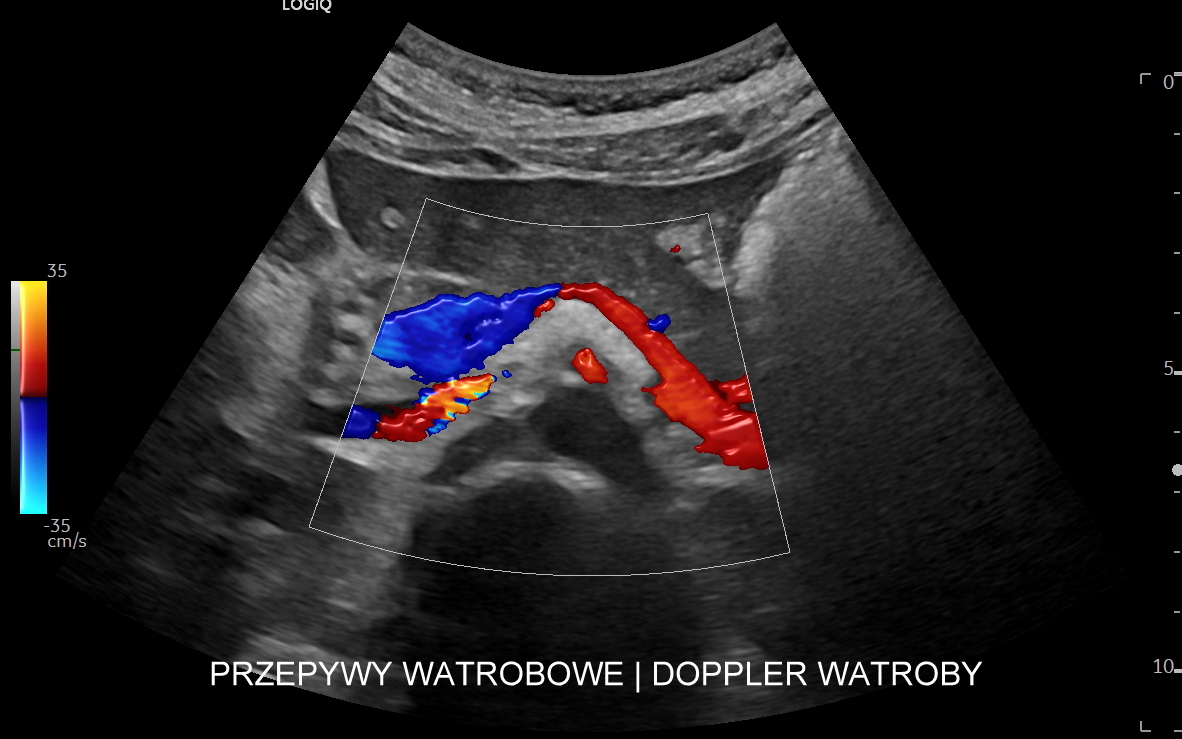

Wątroba to jeden z najważniejszych organów człowieka, posiada wiele kluczowych funkcji, a życie bez niej nie jest możliwe. Wątroba jest głównym centrum metabolicznym organizmu, gromadzi zapasy energetyczne, pełni funkcje detoksykacyjne, produkuje czynniki krzepnięcia oraz substancje niezbędne do trawienia pokarmów. Diagnostyka medyczna wątroby jest wielotorowa. Prawidłowość jej funkcji ocenia się w diagnostyce laboratoryjnej poprzez oznaczenie takich parametrów jak AST, ALT, GGTP, ALP, INR, APTT, glukoza, lipidogram. Laboratoryjne parametry zapalne dotyczące wątroby to m. in. HBs-Ag, a/HCV. Miąższ wątroby ocenia się w klasycznym badaniu USG, badaniu elastograficznym 2D-SWE oraz w badaniu stłuszczenia QUS. Naczynia krwionośne wątroby oceniane są z kolei w badaniu Dopplerowskim przepływów wątrobowych.

Wątroba posiada unaczynienie różnego typu, a każde o swojej indywidualnej charakterystyce. Są to unaczynienie tętnicze, unaczynienie wrotne (żyła wrotna i jej dopływy z narządów jamy brzusznej), odpływ żylny poprzez żyły wątrobowe. W USG Doppler przepływów wątrobowych bada się każdy z tych układów.